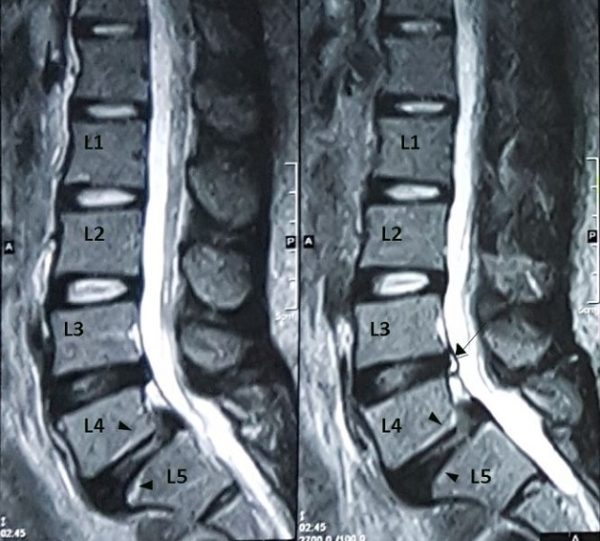

Thoát vị đĩa đệm đĩa đệm là tình trạng đĩa đệm lệch hoặc trượt ra khỏi vị trí ban đầu, làm cho phần nhân nhầy bên trong đĩa đệm thoát ra ngoài. Điều này gây chèn ép dây thần kinh và tủy sống, tạo nên những cơn đau dai dẳng, đặc biệt khi vận động. Hai dạng thoát vị đĩa đệm thường gặp đó là ở thắt lưng và thoát vị đĩa đệm cột sống cổ.

Thoát vị đĩa đệm đẩy nhân nhầy lệch ra khỏi vị trí ống sống, gây chèn ép đường đi của thần kinh, mạch máu, tủy sống xung quanh xương sống. Khi người bệnh vận động, sự cọ xát giữa các sợi thần kinh, ống sống và tủy sống, mạch máu gây cảm giác đau nhói, đau nhức tê bì cánh tay, mất cảm giác. Khi chèn ép vào dây thần kinh lâu ngày có thể làm mất kiểm soát đại tiểu tiện, teo cơ cứng khớp. Thiếu nuôi dưỡng lâu ngày có thể gây tổn thương không hồi phục.